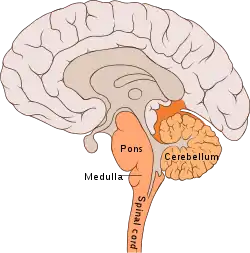

The cerebellum ("little brain") is a structure located at the rear of the brain, near the spinal cord. It looks like a miniature version of the cerebral cortex, in that it has a wavy, or convoluted surface.[3]

This separation makes sense if the cerebellum, which is far removed from the hippocampus, is responsible for procedural learning. The cerebellum is more generally involved in motor learning, and damage to it can result in problems with movement, specifically it is considered to co-ordinate timing and accuracy of movements, and to make long-term changes (learning) to improve these skills.[1]